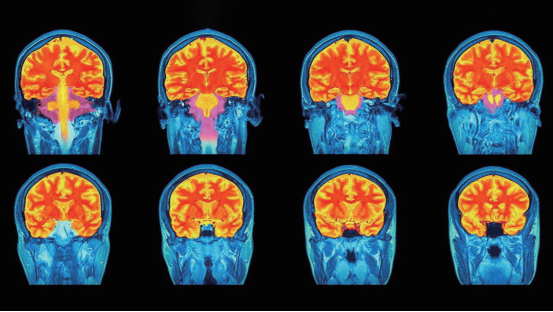

“身体比意识更诚实。” 神经科学家李凌展示着功能性核磁共振对比图:伪装积极的员工在听到“OKR”时,疼痛相关脑区激活程度堪比物理伤害。